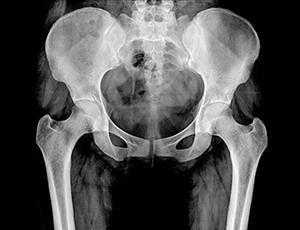

На снимке рентгенограммы должно проявиться симметричное изображение двух половин таза, крестца, межпозвонковых отверстий крестца, а также ветвей лобковых костей и седалищных. Должно отчётливо просматриваться вещество кости, виднеться контуры двух вертлужных впадин и шейки бедренных костей.

Существуют определенные показатели нормы состояния и строения тазобедренного сустава, с которыми при расшифровке сопоставляются фактические данные. Например, угол Виберга в норме должен располагаться между линией центра головки бедра, верхне-наружным краем вертлужной впадины. Нормальная величина угла составляет примерно 30 градусов. Угол наклона входа в вертлужную впадину также имеет норму - 31-42 градуса. Угол шеечно-диафизарный в норме должен быть от 115 до 140 градусов.

Визуализируя гребень подвздошной кости, крестец, подвздошно-крестцовые сочленения, большое тазовое кольцо, лобковую и седалищную кости, проксимальный отдел бедра, рентген таза может показать: анатомические нарушение формы таза или тазобедренного сустава; переломы таза; перелом, вывих или артрит тазобедренного сустава; опухоли костей таза (остеосаркомы).